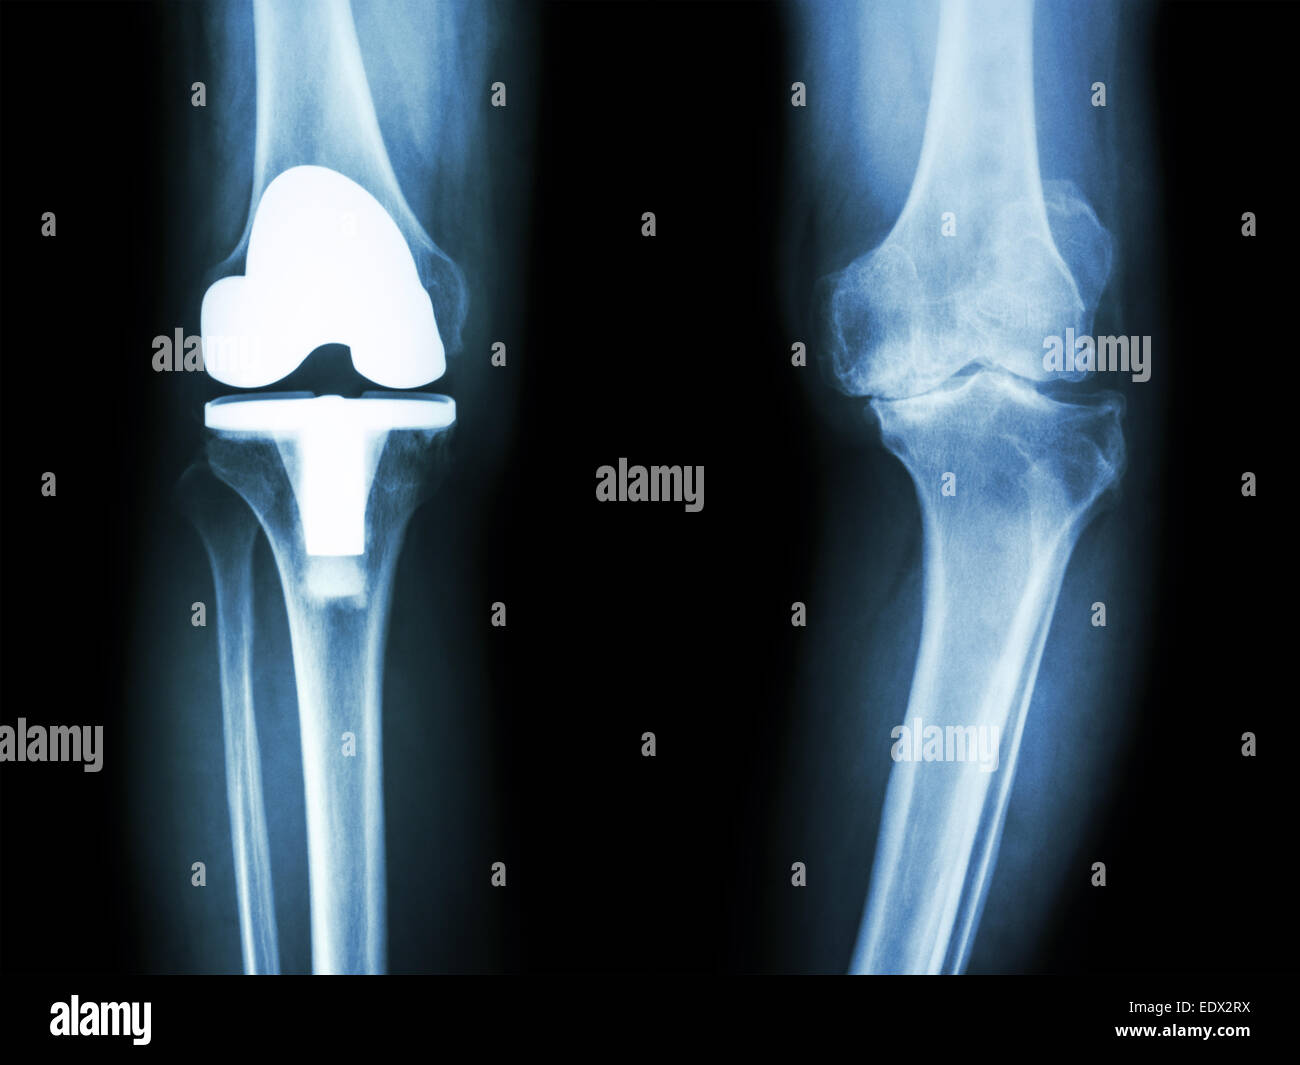

Film x-ray de l'arthrose du genou genou articulation artificielle et patient Banque D'Imageshttps://www.alamyimages.fr/image-license-details/?v=1https://www.alamyimages.fr/photo-image-film-x-ray-de-l-arthrose-du-genou-genou-articulation-artificielle-et-patient-77404991.html

Film x-ray de l'arthrose du genou genou articulation artificielle et patient Banque D'Imageshttps://www.alamyimages.fr/image-license-details/?v=1https://www.alamyimages.fr/photo-image-film-x-ray-de-l-arthrose-du-genou-genou-articulation-artificielle-et-patient-77404991.htmlRFEDX2RY–Film x-ray de l'arthrose du genou genou articulation artificielle et patient

Film x-ray de l'arthrose du genou genou articulation artificielle et patient Banque D'Imageshttps://www.alamyimages.fr/image-license-details/?v=1https://www.alamyimages.fr/photo-image-film-x-ray-de-l-arthrose-du-genou-genou-articulation-artificielle-et-patient-77404992.html

Film x-ray de l'arthrose du genou genou articulation artificielle et patient Banque D'Imageshttps://www.alamyimages.fr/image-license-details/?v=1https://www.alamyimages.fr/photo-image-film-x-ray-de-l-arthrose-du-genou-genou-articulation-artificielle-et-patient-77404992.htmlRFEDX2T0–Film x-ray de l'arthrose du genou genou articulation artificielle et patient

Film x-ray de l'arthrose du genou genou articulation artificielle et patient Banque D'Imageshttps://www.alamyimages.fr/image-license-details/?v=1https://www.alamyimages.fr/photo-image-film-x-ray-de-l-arthrose-du-genou-genou-articulation-artificielle-et-patient-77404990.html

Film x-ray de l'arthrose du genou genou articulation artificielle et patient Banque D'Imageshttps://www.alamyimages.fr/image-license-details/?v=1https://www.alamyimages.fr/photo-image-film-x-ray-de-l-arthrose-du-genou-genou-articulation-artificielle-et-patient-77404990.htmlRFEDX2RX–Film x-ray de l'arthrose du genou genou articulation artificielle et patient